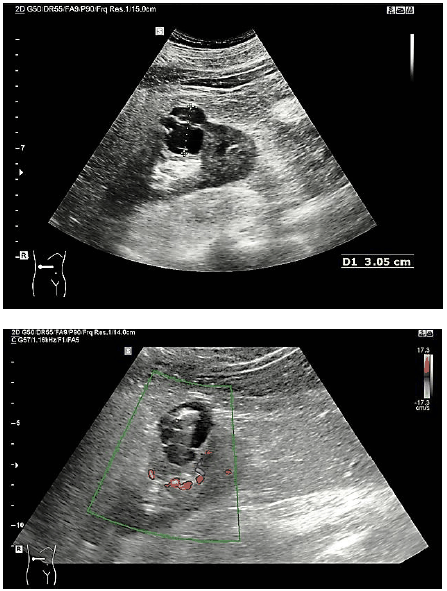

Paciente, 38 anos, sexo masculino, comparece para realizar ultrassonografia abdominal. Assintomático; exame solicitado para perícia médica em concurso público, em que foram observadas as seguintes imagens:

Considerando o caso hipotético, assinale a classificação dessa lesão de acordo com a classificação de Bosniak.